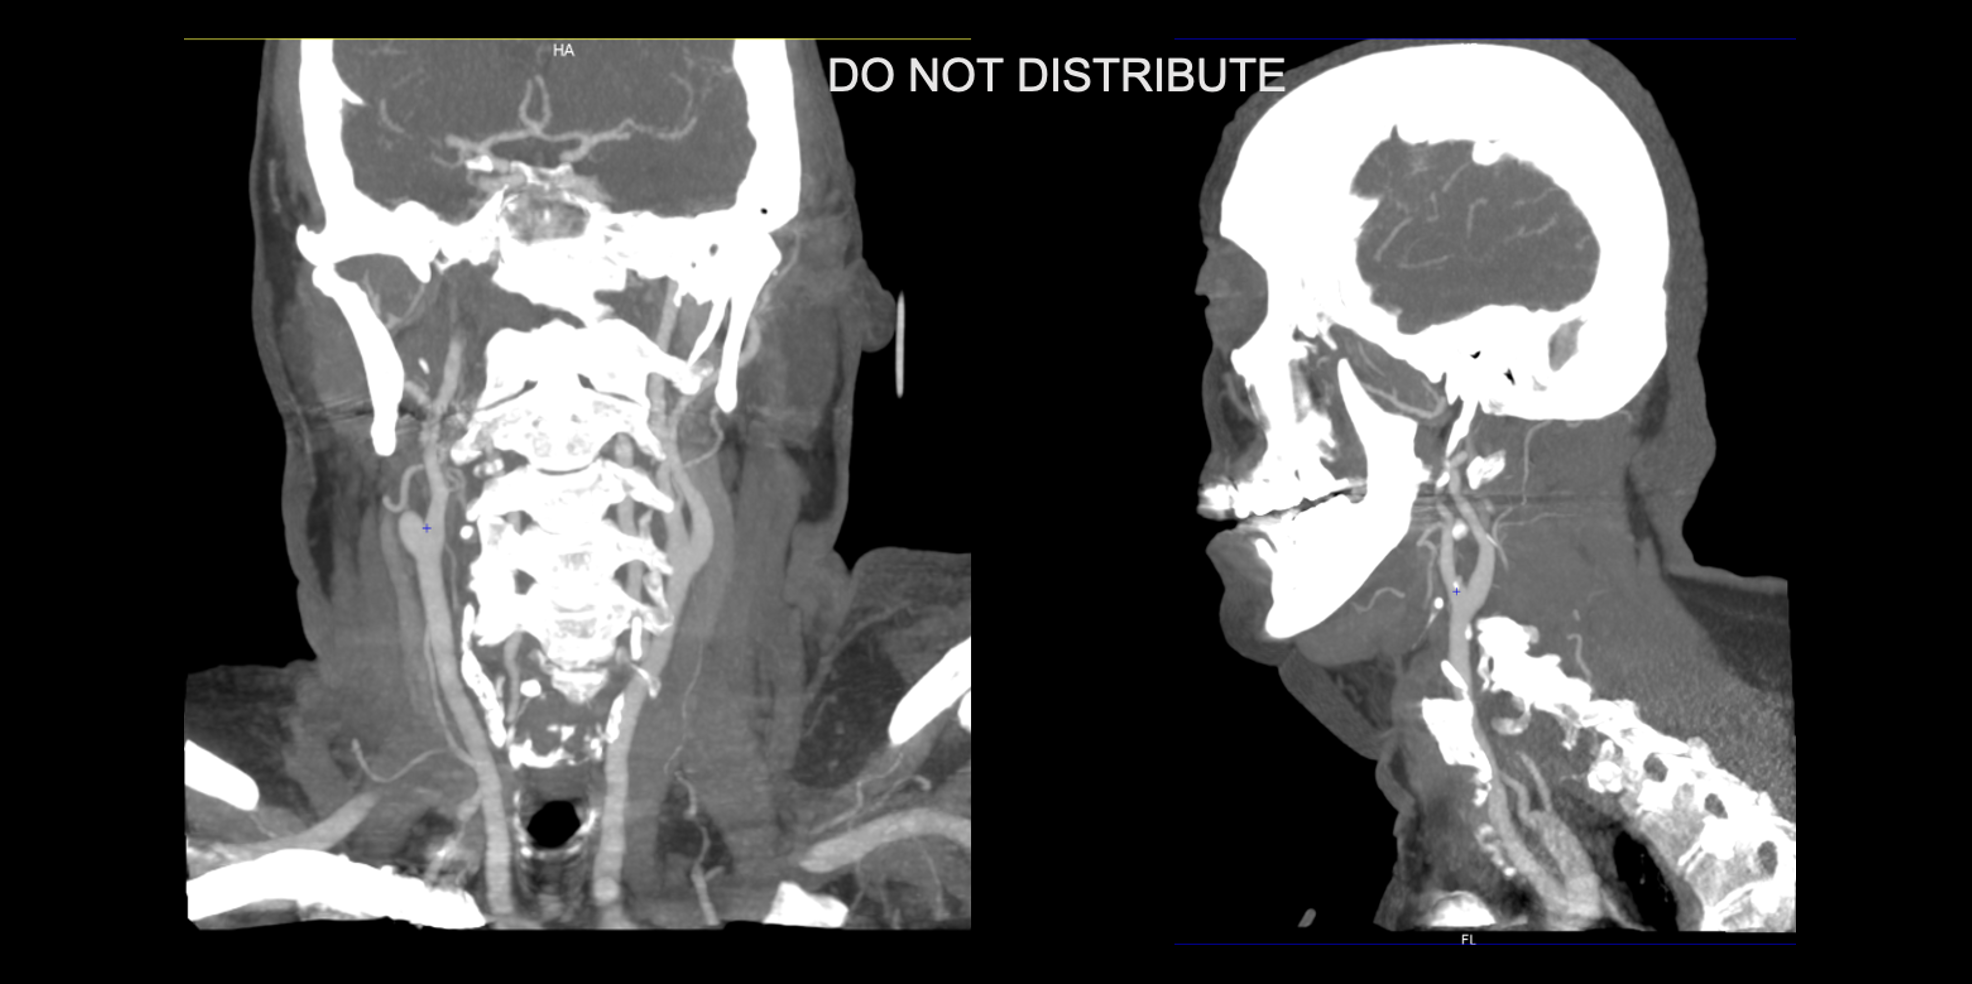

Myelin water imaging in Anti-NMDA receptor autoimmune encephalitis; a pilot study

Background

This study explored whether Myelin Water Imaging could detect myelin injury in Anti-NMDA receptor autoimmune encephalitis (NMDAr-AIE), where traditional neuroimaging is often normal. Myelin Water Fraction (MWF) quantifies myelin content by distinguishing myelin sheath water from other brain water compartments.

Methods

Adult participants with confirmed NMDAr-AIE diagnoses and healthy controls (HC) underwent 3T brain MRI (Magnetic Resonance Imaging) including MWF mapping. Participants were recruited after discharge from the hospital. Mean MWF was calculated for 4 white matter regions of interest (ROI). MHI (Myelin heterogeneity Index) was calculated by dividing the MWF standard deviation by the mean MWF. Patient demographics, clinical assessments, treatment, and outcomes were collected.

Results

Five participants with NMDAr-AIE (4F/1M, mean age 30, SD 7) and four HC (3F/1M, mean age 36, SD 6) were included. All NMDAr-AIE participants had normal or non-specific T2 hyperintensities on initial imaging and had received immunotherapy. The mean Modified Rankin Score (MRS) on discharge was 2. MWF (mean ± SD) for normal-appearing white matter, corpus callosum, corticospinal tract, and superior longitudinal fasciculus were 0.10±0.02, 0.12±0.02, 0.15±0.03, 0.12±0.02, which were very similar to HC at 0.09±0.02, 0.11±0.01, 0.15±0.02, and 0.11±0.02, respectively.

Fig. 1 Myelin Water Imaging of two selected patients

Screenshot 2025 06 01 at 12.05.23 pm

Conclusions and Future Direction

Myelin Water Imaging showed no myelin pathology in five NMDAr-AIE patients, with MWF and MHI values comparable to HC, suggesting that myelin pathways are relatively preserved post-recovery from AIE. Moving forward, we aim to continue recruiting healthy controls, patients post-recovery and those experiencing active disease to determine if there are any MWF abnormalities throughout the disease course. Future studies are needed to assess MWF changes in other antibody-mediated encephalitides.